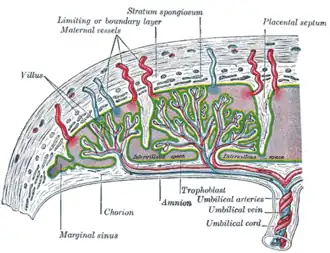

The chorion consists of two layers: an outer formed by the trophoblast, and an inner formed by the extra-embryonic mesoderm.

The trophoblast is made up of an internal layer of cubical or prismatic cells, the cytotrophoblast or layer of Langhans, and an external multinucleated layer, the syncytiotrophoblast.

The chorion undergoes rapid proliferation and forms numerous processes, the chorionic villi, which invade and destroy the uterine decidua, while simultaneously absorbing nutritive materials from it for the growth of the embryo.

The chorionic villi are at first small and non-vascular, and consist of the trophoblast only, but they increase in size and ramify, whereas the mesoderm, carrying branches of the umbilical vessels, grows into them, and they are vascularized.

Blood is carried to the villi by the paired umbilical arteries, which branch into chorionic arteries and enter the chorionic villi as cotyledon arteries. After circulating through the capillaries of the villi, the blood is returned to the embryo by the umbilical vein. Until about the end of the second month of pregnancy, the villi cover the entire chorion, and are almost uniform in size; but, after this, they develop unequally.

Scheme of placental circulation.

Scheme of placental circulation.